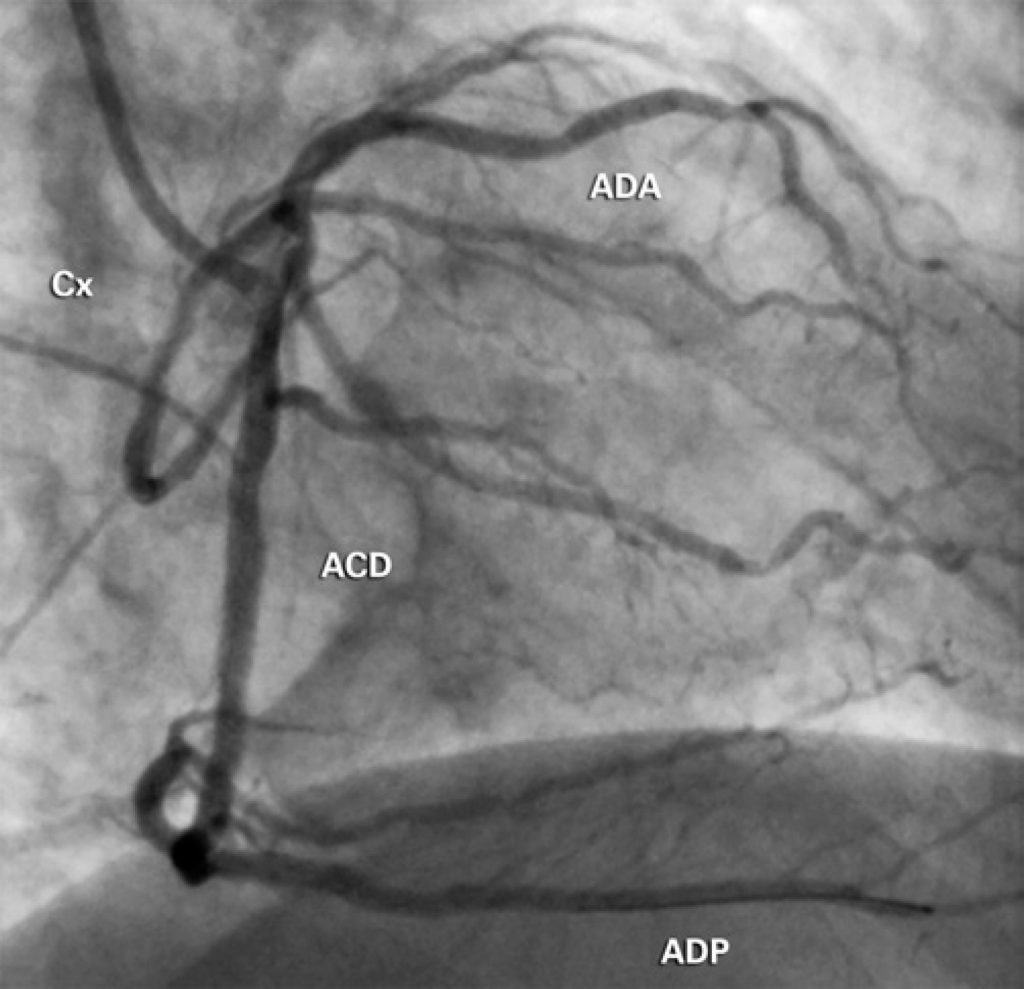

A artéria coronária única é uma anomalia coronariana congênita rara, que pode estar associada à morte súbita. Reportamos um caso de artéria coronária única associado com doença arterial coronariana aterosclerótica multiarterial, que foi tratado de forma bem-sucedida, por meio de intervenção coronariana percutânea com implante de stents farmacológicos.